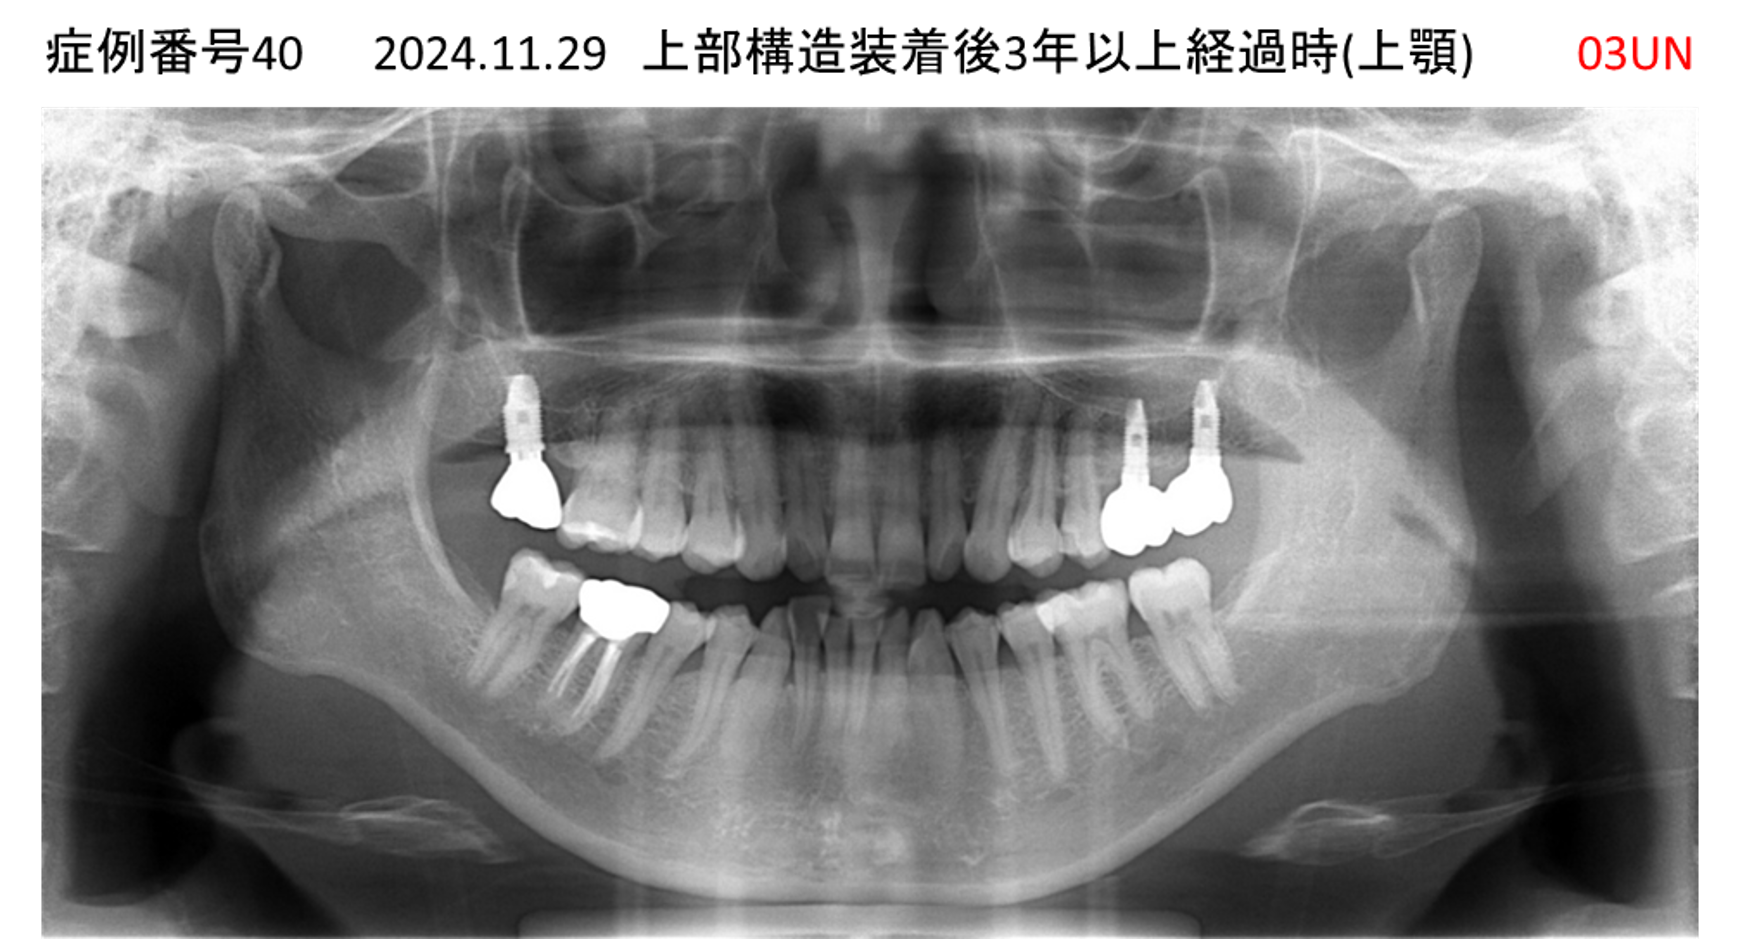

義歯が合わない、噛めない患者様のインプラント症例

| 治療名称 |

インプラントコーヌステレスコープ |

| 治療費用 |

270万円+税 |

| 治療期間 |

4か月 |

| 患者さんの症状(主訴) |

義歯が合わない、噛めない |

| 治療内容 |

インプラント、義歯作製(コーヌステレスコープ) |

| 治療結果 |

しっかり噛めるようになった。見栄えが良くなった。 |

| 治療の注意点(リスク/副作用) |

義歯が壊れた場合、インプラントが壊れた場合は再治療が必要 |